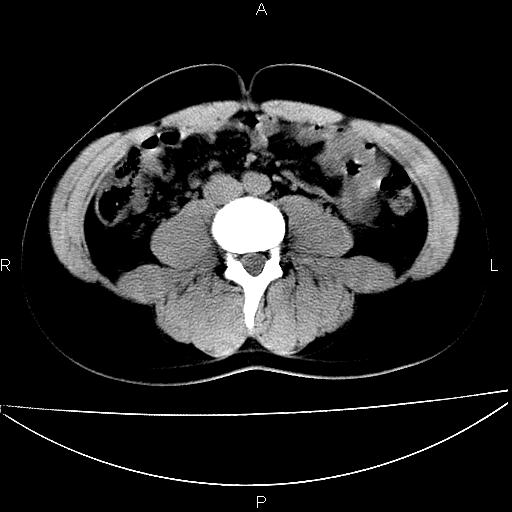

标题: CT29462:双测输尿管扩张

男 25岁 自述 尿频尿急,排尿困难20多天.无腰痛, b超说左肾盂轻度积水,左输尿管上端扩张.未见结石影. ct我看双侧肾盂轻度积水,双输尿管上端都扩张,大家看看能看见结石吗?

考虑肾外肾盂 前列腺轻度肿大 密度欠均 考虑炎性改变

箭头所指不是输尿管,壶腹型肾盂。

肾外肾盂,必要时+c